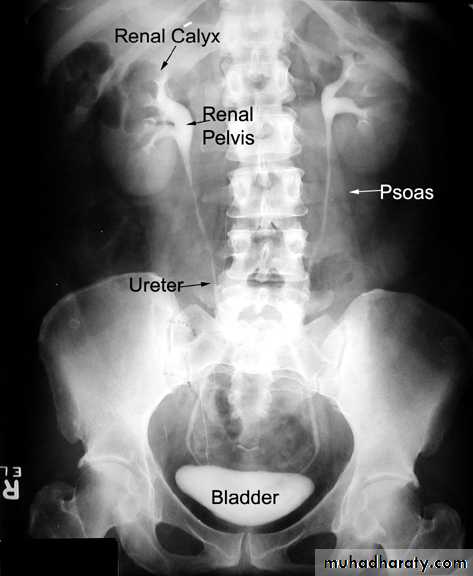

EXCRETORY UROGRAPHY (IVU , IVP, EXU )

These are organic chemicals to which iodine atoms are attached to absorb X-rays.Allows visualization of the entire urinary tract. The study provides demarcation of the renal parenchyma, the pelvicalyceal system, ureters, and bladder, providing both anatomic and functional information.

Number, size, site, function of the kidneys, anatomy of the collecting system, hydronephrosis, and filling defects, stones.

Intravenous urography (IVU)

- After a plain film, iodine-containing contrast medium is injected intravenously and serial films are taken to follow its excretion by the kidneysThe nephrogram phase - on the initial film 1-3 minutes after injection, contrast medium is in the glomeruli and proximal tubules so that a clear image of the renal outline is obtained

The pyelogram phase - subsequent excretion of contrast medium outlines the collecting systems, renal pelvis, ureter and bladder, showing any structural abnormalities or filling defects